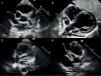

Echocardiogram (modified high parasternal short-axis view at the level of the large arteries for assessment of aortic arch and coronary arteries) revealing the presence of giant aneurysms in the proximal segments of the three major coronary arteries (images 1 and 2). Follow-up echocardiogram showing intraluminal thrombi in the LAD and RCA, with preserved systolic function (images 3 and 4).

In most patients, coronary abnormalities were first detected by Doppler echocardiography in most patients (Fig. 1), except in one patient (case 4) in whom viral illness was initially suspected and the first diagnostic test was a chest CT scan requested due to the presence of infiltrates in both upper lobes that detected coronary abnormalities, which were later confirmed by echocardiography. In all cases, imaging detected abnormalities in more than one artery.